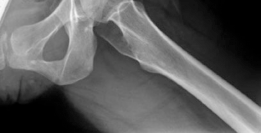

Radiographic and Advanced Imaging

Standard preoperative imaging must include an anteroposterior (AP) pelvis, cross-table lateral, and false-profile view of the affected hip. These evaluate for dysplasia, impingement morphology (cam/pincer), and degenerative changes.

Magnetic Resonance Arthrography (MRA) is the gold standard for evaluating the capsuloligamentous complex. Extravasation of contrast anteriorly often delineates the size and location of the capsular defect. MRA also assesses labral integrity, chondral damage, and the viability of the femoral head. A 3D computed tomography (CT) scan is highly recommended to quantify femoral anteversion and acetabular version, as unrecognized osseous malorientation (e.g., severe femoral retroversion) will predispose the reconstruction to failure if not addressed concurrently with a derotational osteotomy.